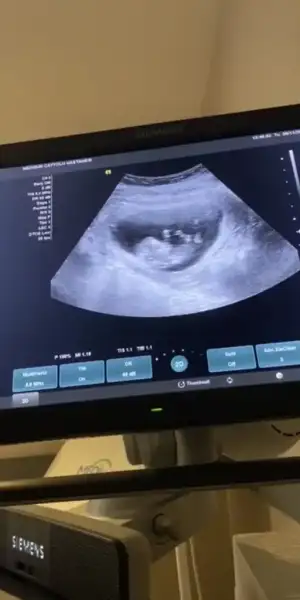

Biri 9+5 biri de 11+5. Yan donmus gibi belli oluyor mu bilemedimTekrar atsana foto

Kız gibiBiri 9+5 biri de 11+5. Yan donmus gibi belli oluyor mu bilemedim![]()

Ikra erkek gibi dedi sen de kizKız gibi

Bende baştan erkek yaZdım sonra kız dedimIkra erkek gibi dedi sen de kizbakalim hangisi olacak cokkk tesekkurler